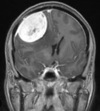

Metástases cerebrais Pontos hipertenso com edema perilesional